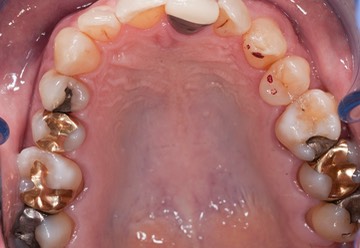

Photos of Clinical Operations

_DSC6281